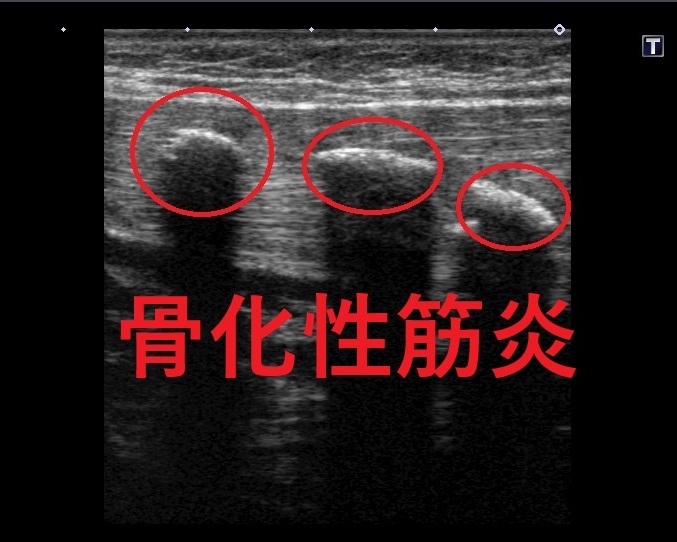

下の写真が筋肉内にでき骨化性筋炎のエコー画像にです!

赤丸で囲んだ部分が骨性の物質です。

骨は硬い組織のため、エコーのビームがそこから先に落ちないので

骨化部分の下は黒く映るんです(*_*;

本来、この場所にはないものなので

運動をしたときに痛みや、違和感があります!![]()